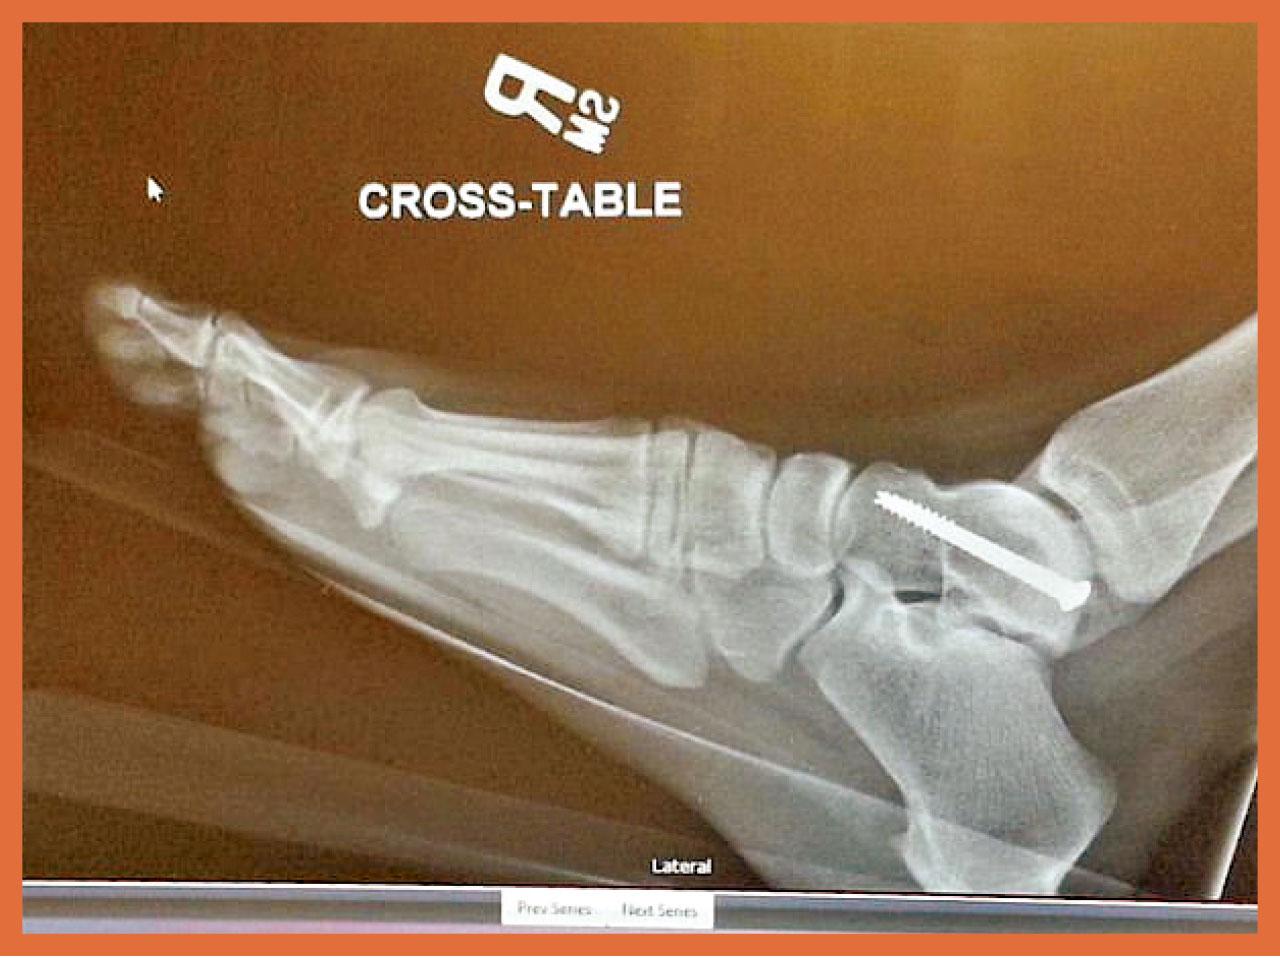

下半身傷勢更嚴重:大腿骨4處折斷,足踝爆裂。其時夫女無恙落車,她則周身傷動彈不得,愁爆待援(圖)。盆骨、膝蓋與踝骨各鑲2釘終算「嵌番埋一齊」,惟事隔兩年仍未恢復元氣,她至今不可久站或走遠路。Tatum現發起眾籌,非為己療傷,而是在路邊廣設警告牌:切勿蹺腿坐車!